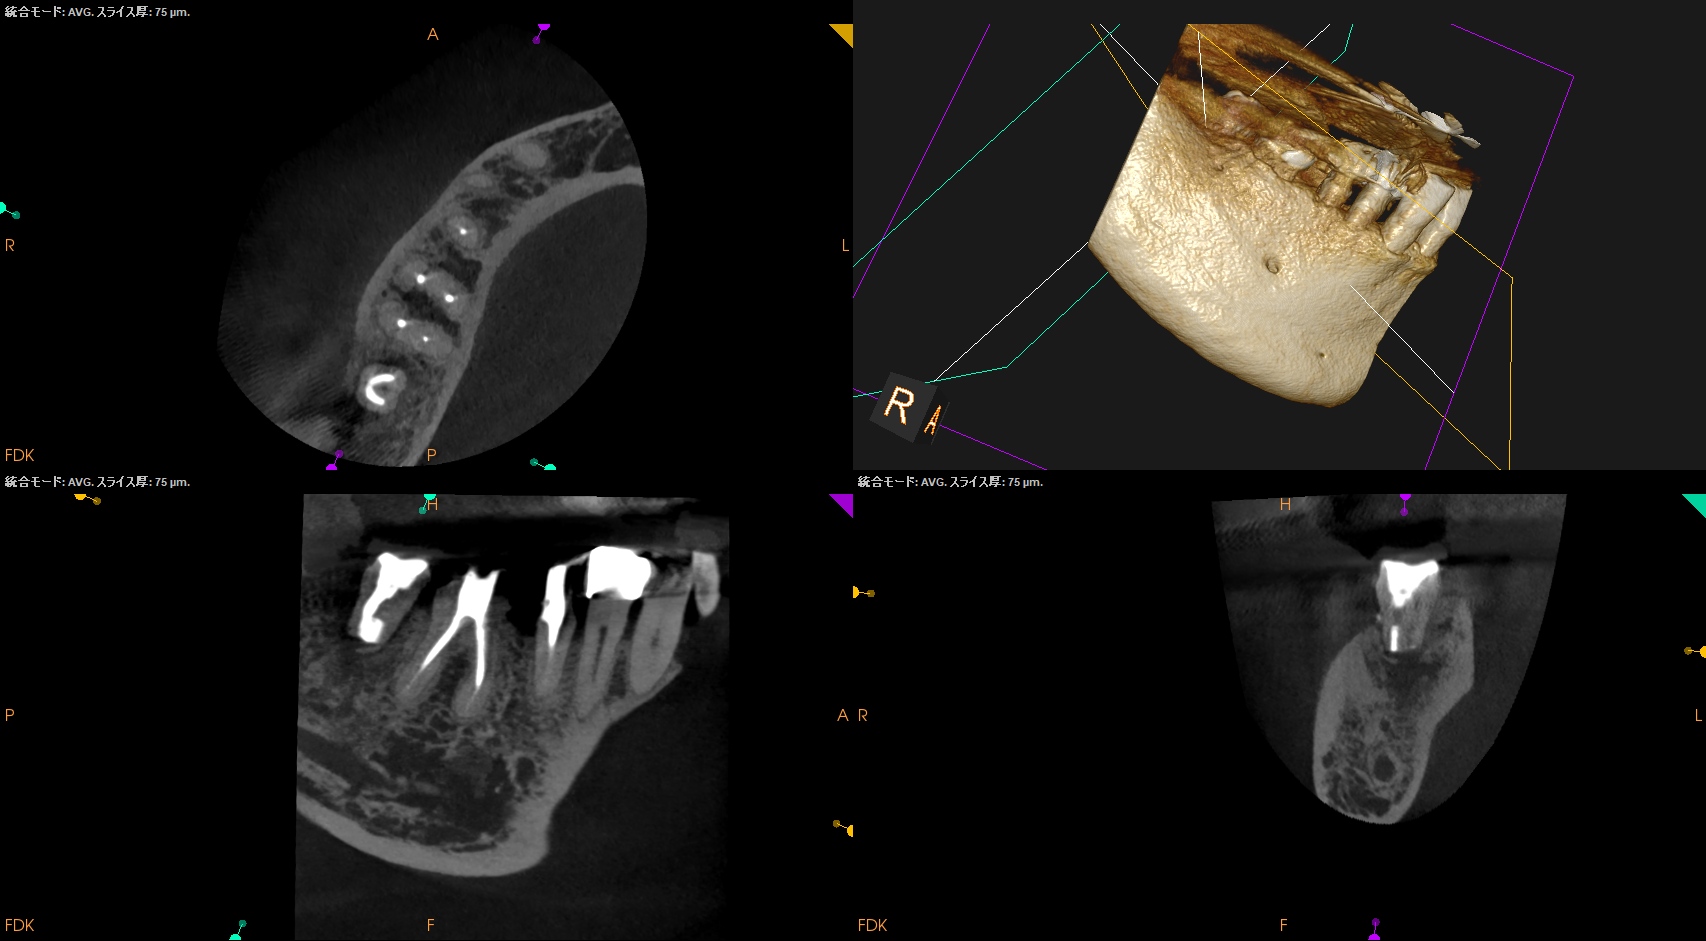

#31 Intentional Replantation 7M recall(2025.12.23)

術前の腫脹、頬側のMBの4mm, Bの6mmの歯周ポケット、歯牙の軽度動揺、咬合痛・圧痛は消失した。

初診時と比較した。

劇的に状態は改善した。

特に、この歯牙の術前の動揺と頬側の深い歯周ポケットはエンドの問題が原因でできていたようだ。

このような時に、

ペリオの治療をすると歯周ポケットはより深くなる

ことが文献では知られている。

この業界は常に

ペリオ<エンド

なのである。